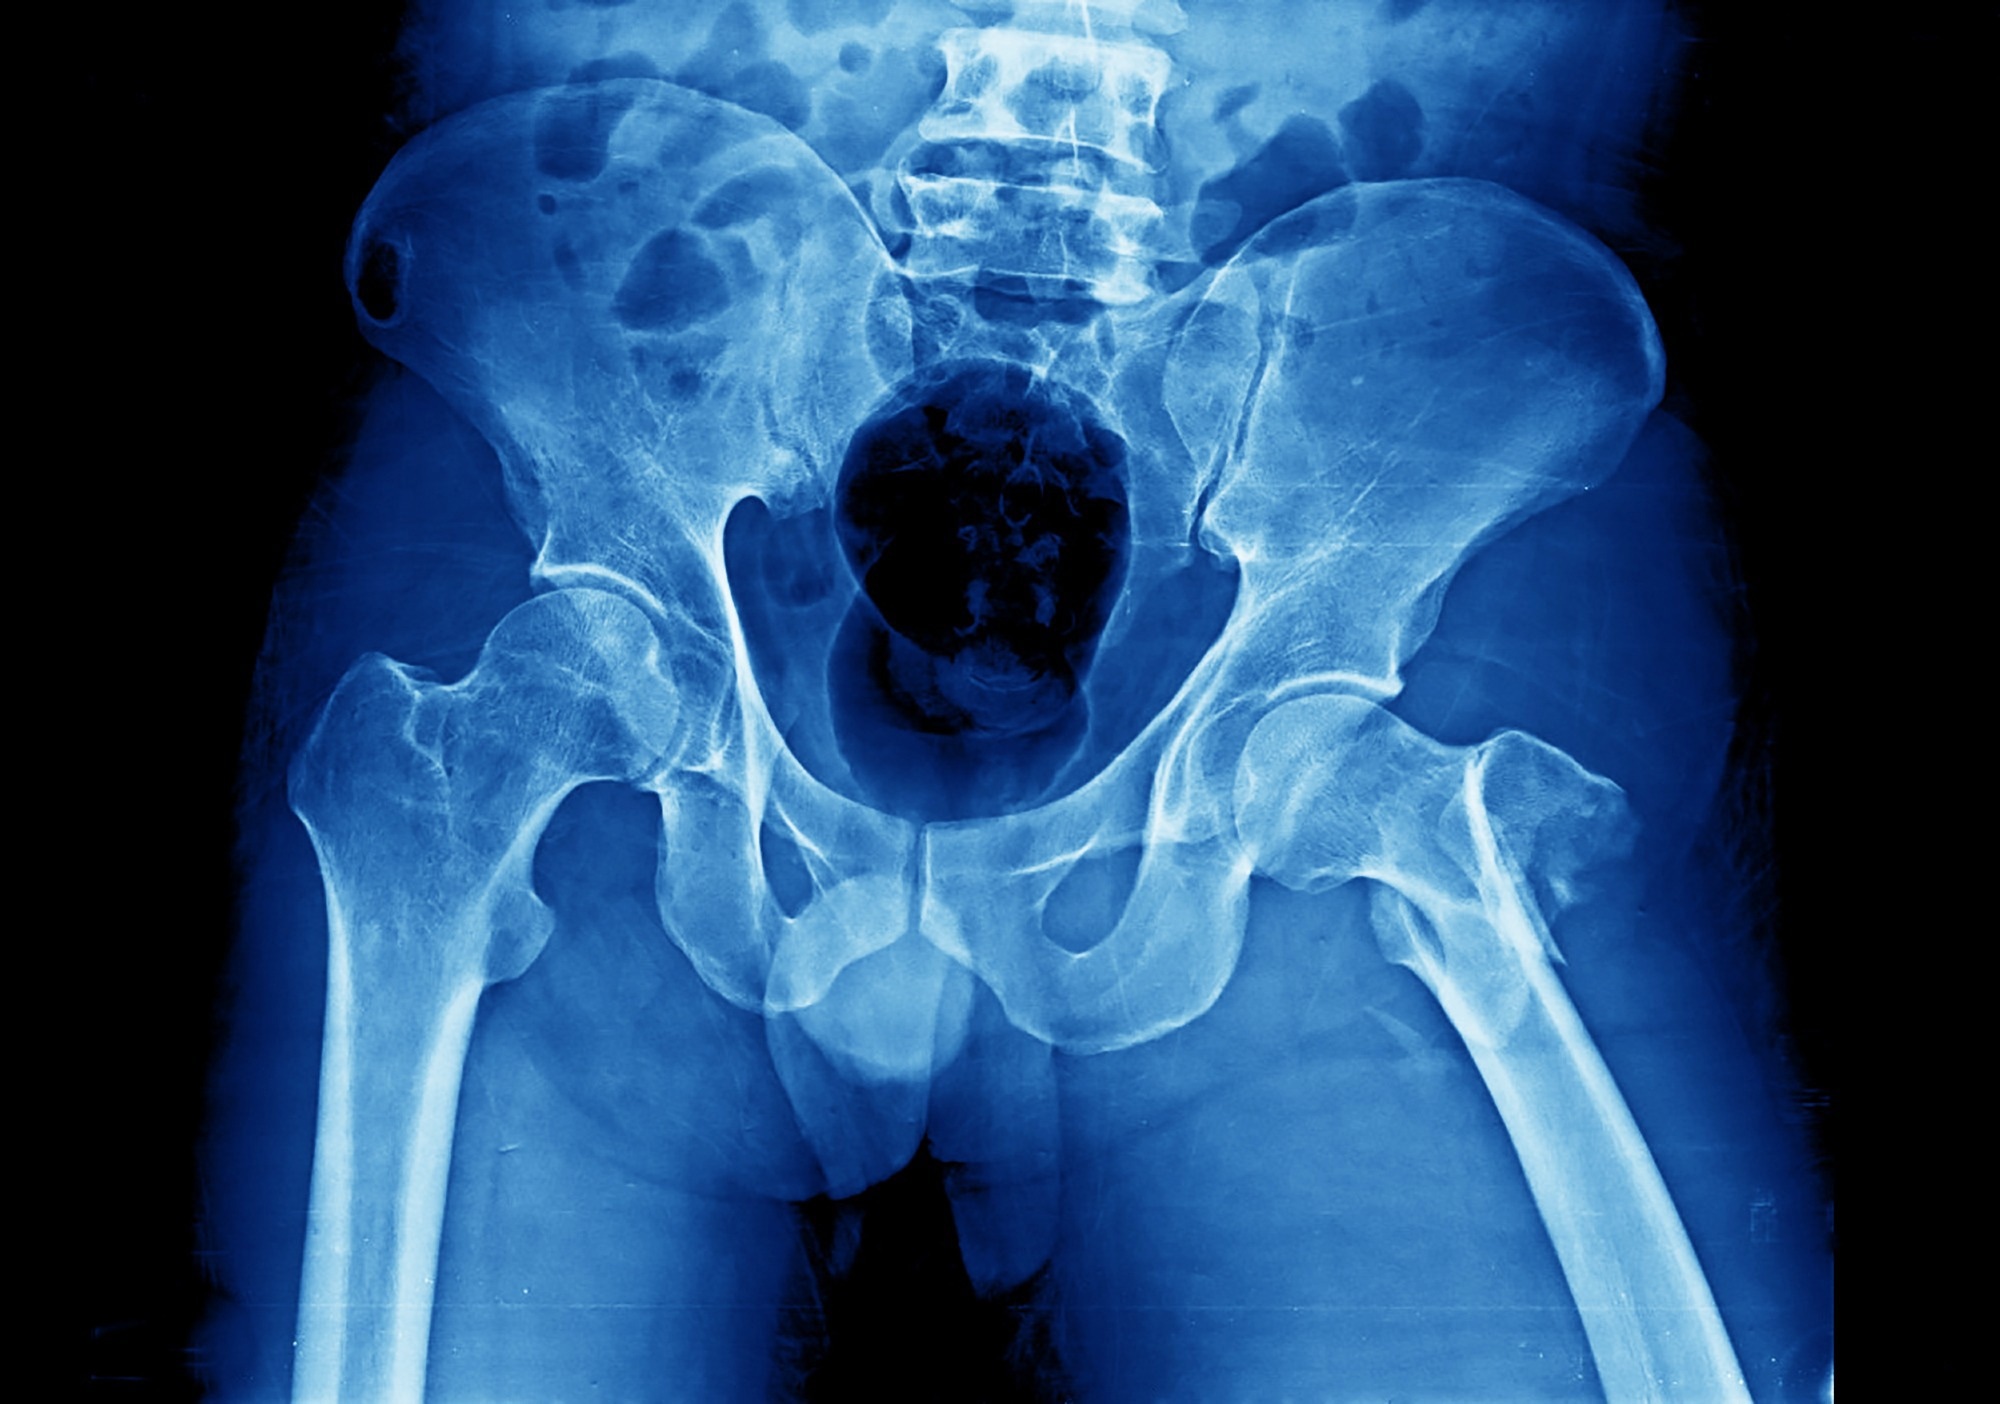

Study: ‘Skeletal Age’ for mapping the impact of fracture on mortality. ​​​​​​​Image Credit: Yok_onepiece / Shutterstock​​​​​​​Study: ‘Skeletal Age’ for mapping the impact of fracture on mortality. ​​​​​​​Image Credit: Yok_onepiece / Shutterstock